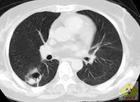

其他輔助檢查:X線表現:①通常為肺段及肺葉實變。②呈支氣管肺炎,表現為斑片狀或多葉性浸潤,很少形成肺膿腫,約20%發生膿胸。